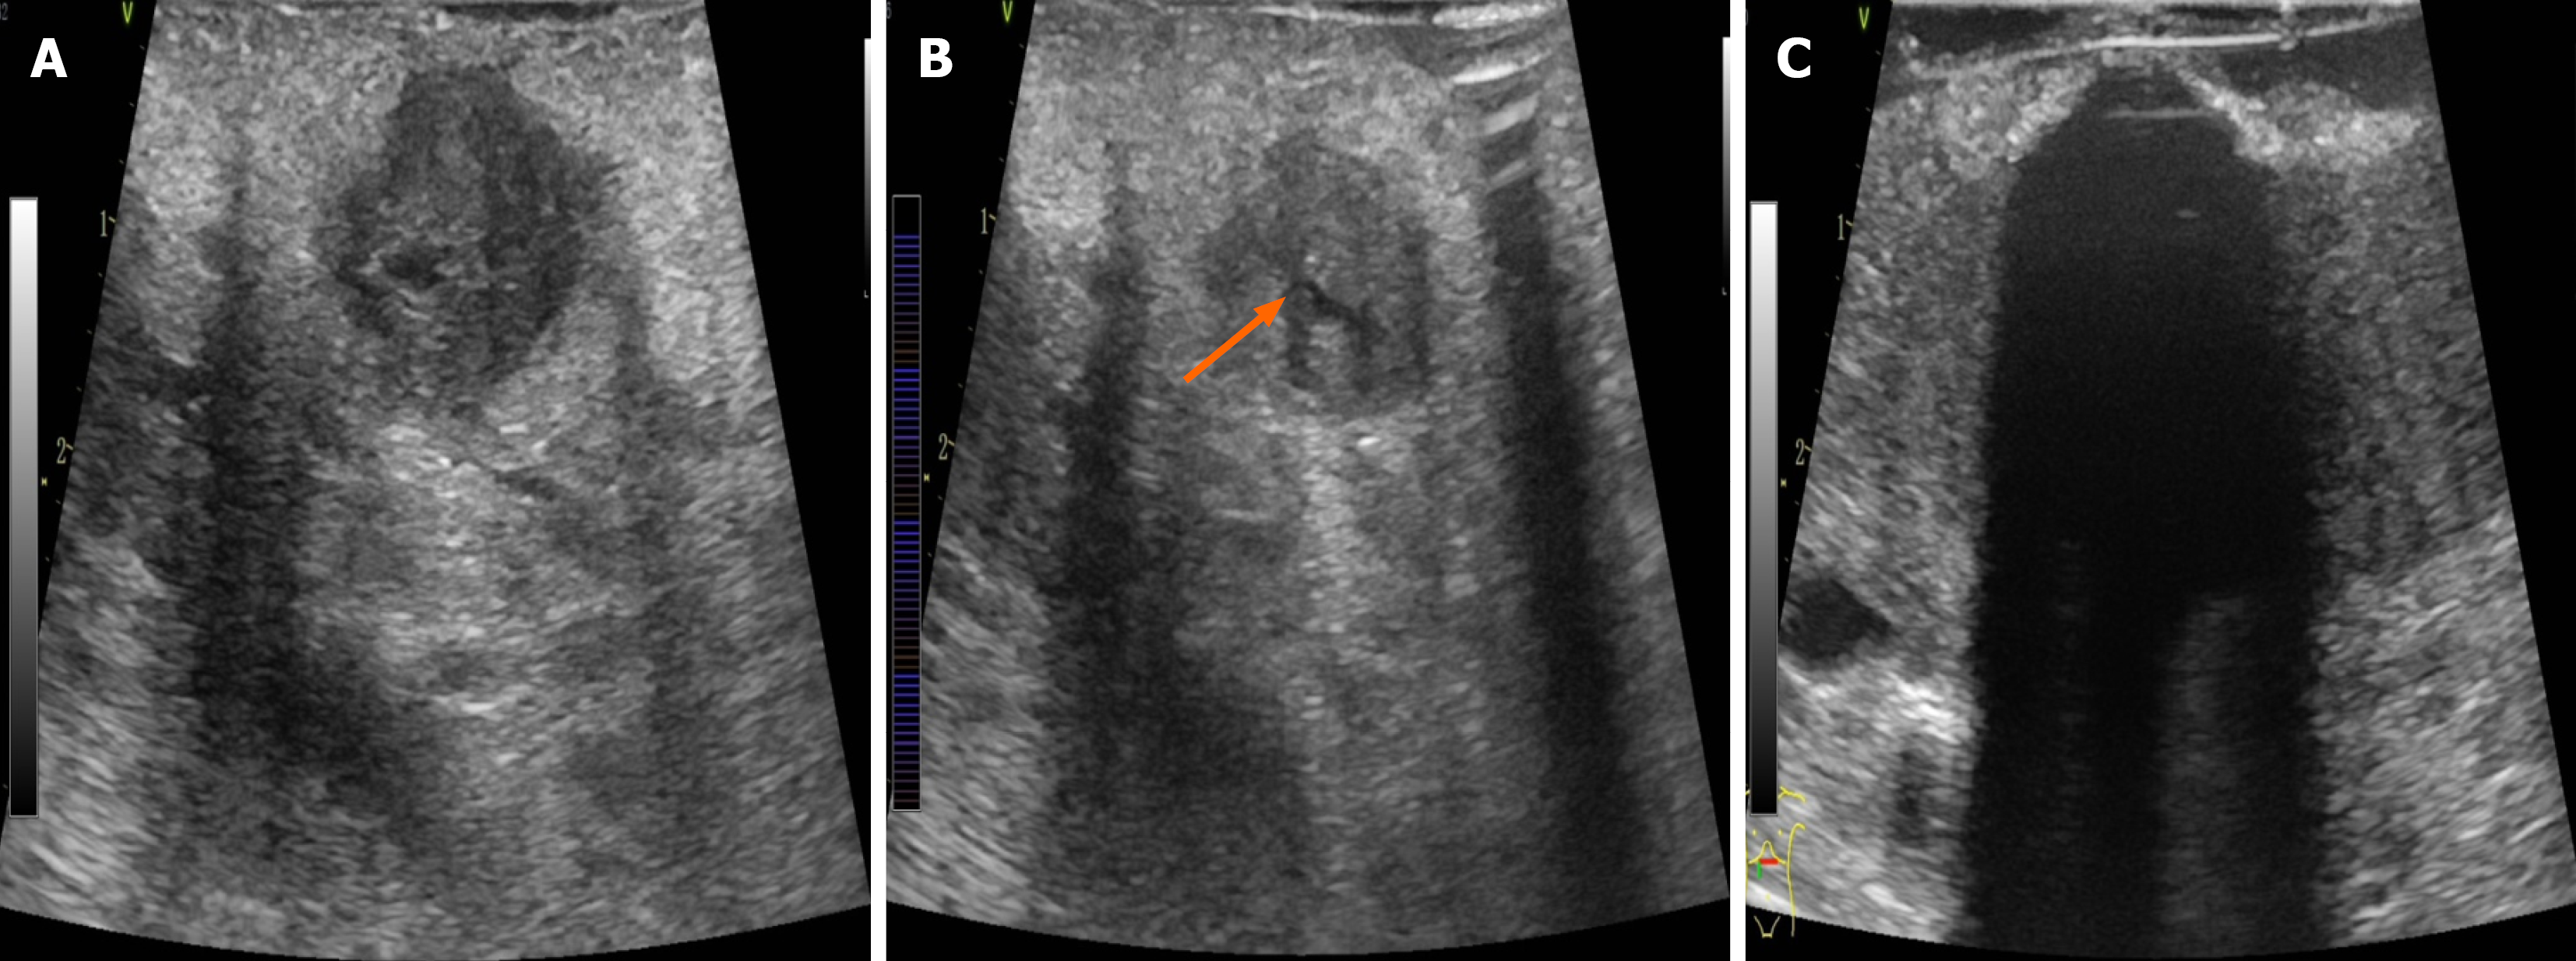

After the tumor location, size, and vascular/ductal relationships were identified by ultrasound, an ablation plan was developed to determine the needling site/direction, freezing duration, and therapeutic cycles. The 8 MHz linear array probe was used to explore the location of the tumor and its relationship with important structures such as blood vessels, biliary and pancreatic ducts, and duodenum to determine the puncture site, angle, and needle depth. During intraoperative ultrasound examination, the SMA/SMV, splenic artery and vein, portal vein, common hepatic artery, gastroduodenal artery, common bile duct, and pancreatic duct were exposed. Care should be taken to avoid injury during puncture and freezing. It was worth noting that when the portal vein-SMV or splenic vein is invaded, it will lead to systemic or regional portal hypertension, and varicose thickening of the peripancreatic vein. LAPC is usually combined with pancreatic duct dilatation, especially when puncture is performed. Cryoablation has a unique “hot pool effect”. The large blood vessels will expand with cold stimulation, the blood flow rate will accelerate, and the cold energy will be taken away quickly. Therefore, during the cryoablation process, large blood vessels above 3 mm should not be frozen and destroyed so as to avoid the damage of major blood vessels. This is the unique advantage of cryoablation in the treatment of LAPC. Typically, a 17-G 01HW1530 L needle was inserted under ultrasound guidance up to the tumor base (Figure 1A and B). The cryoablation system was initiated to rapidly freeze the target area to -140 °C to -160 °C, which took 5-15 minutes; subsequently, rewarming mode (approximately 3 minutes) was initiated to heat the target area to > 30 °C, thus completing one treatment cycle. During cryoablation, the ice ball was initially ellipsoidal in shape but became more rounded with longer treatment time. During freezing, the puncture site was continuously rinsed with flowing water to prevent frostbite injury to the surrounding tissues. The size of the ice ball and its relationships with the tumor and surrounding structures were monitored with ultrasound throughout freezing, thus ensuring satisfactory coverage (i.e., reaching or exceeding the tumor margins as far as possible without damaging surrounding structures, such as blood vessels, intestines, and bile ducts) (Figure 1C). The ice ball was droplet-shaped and centered on the tip of the needle on the ultrasound image, along with small, pointed, cone-shaped strong echoes at the edge, homogeneous low-amplitude echoes inside, and posterior acoustic shadowing, which gradually expanded to two sides and the rear. The lower edge of the ice ball was difficult to distinguish due to artifacts, so the morphology of the ice ball needed to be observed from multiple angles (Figure 2). Upon completion of freezing, the site was rewarmed to 30 °C for one cycle. Two cycles were typically required. The needle was rotated gently and then withdrawn at a moderate speed. If the ice ball failed to completely cover the margins of the lesion (defined as the edge of the ice ball, > 5 mm beyond the tumor range) after two ablation cycles, the position of the ablation needle was adjusted after rewarming, and an additional cycle was performed. Upon completion of the treatment, a 4-0 Prolene suture was used to close the puncture site to prevent bleeding and pancreatic leakage. For patients with biliary or gastrointestinal obstruction, cryoablation therapy might be followed by palliative cholangiojejunostomy and/or gastrojejunal anastomosis, depending on the situation.